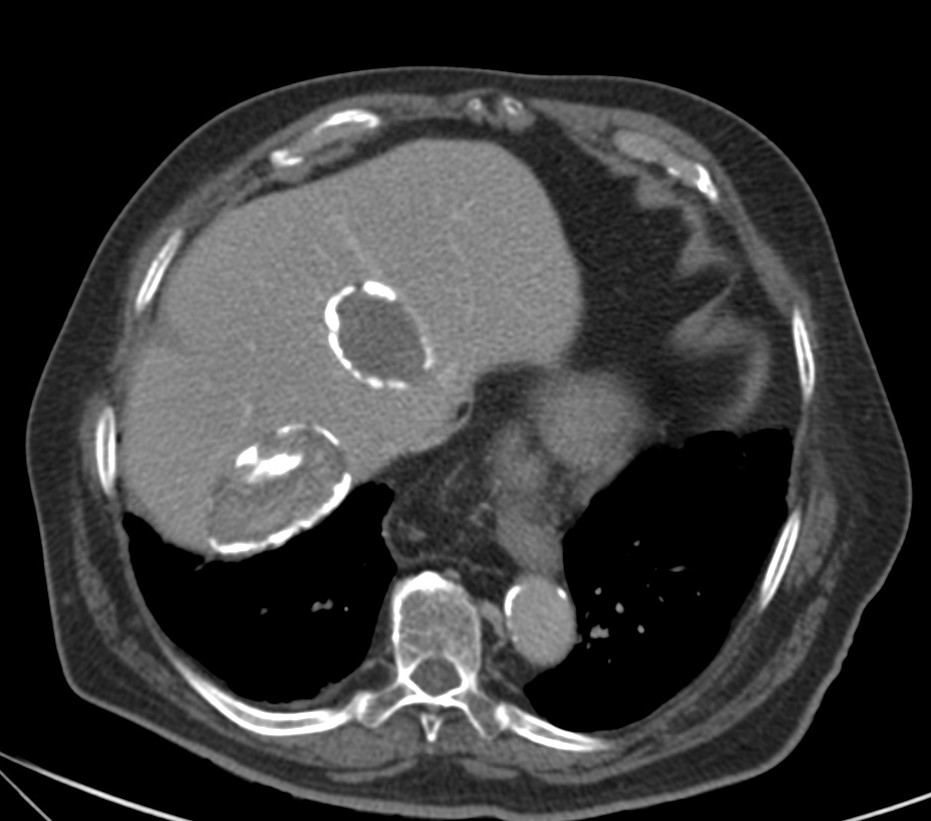

Para ver otro ejemplo:

- TC: Tiene mayor S y E para la valoracion del quiste hidatídico. Se usa cuando la ecografía no nos proporciona un resultado óptimo por obesidad, interposición de gas, cambios postquirúrgicos en la pared abdominal, deformidades, etc… La administración de contraste no es necesaria a menos que se sospechen complicaciones, especialmente la infección o la comunicación con la vía biliar. Los hallazgos por TC son similares a los de ultrasonido, como son la densidad líquido en el interior del quiste, vesículas hijas en la perifería del quiste mayor o madre o calcificación de pared. La pared del quiste muestra alta atenuación inclusive sin contraste y sin calcificación.

La RUPTURA, aunque puede acontecer tras un traumatismo menor, está implícita en la historia natural de la enfermedad y puede ocurrir en el 50 – 90% de los casos, pudiendo pasar desapercibida u originando, en el peor de los casos, una reacción anafiláctica por la antigenicidad del contenido del quiste. La ruptura puede ser contenida, comunicante o directa. En US y TC se observa el paso del contenido a través del defecto de pared que ha producido la ruptura. En la RM se observa la interrupción de la señal hipointensa en T2 del borde del quiste.